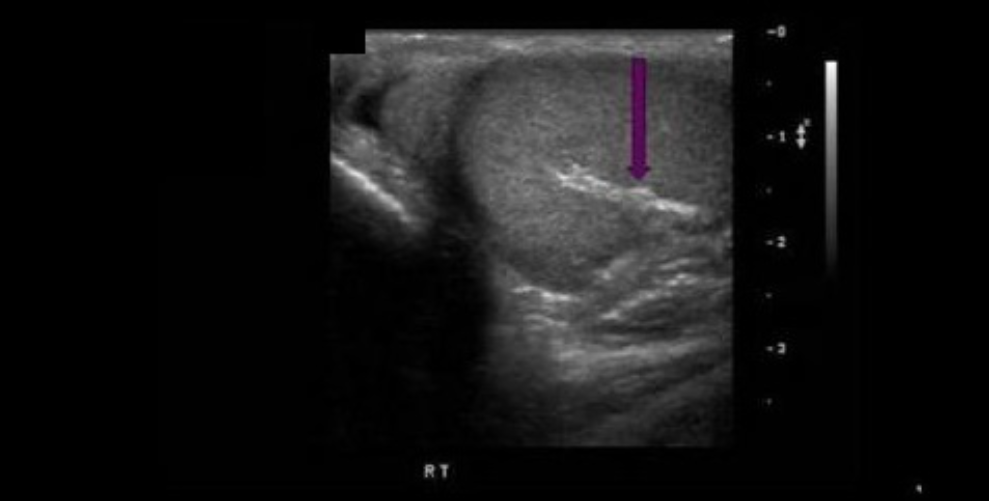

What structure is indicated by the arrow?

D. mediastinum testis

Folds of the tunica albuginea form sections within the testes that converge at a single location called the mediastinum testis (similar to a hilum). The rete testes is a series of channels within the mediastinum. Blood vessels and ductules enter/exit the testicle at the mediastinum.